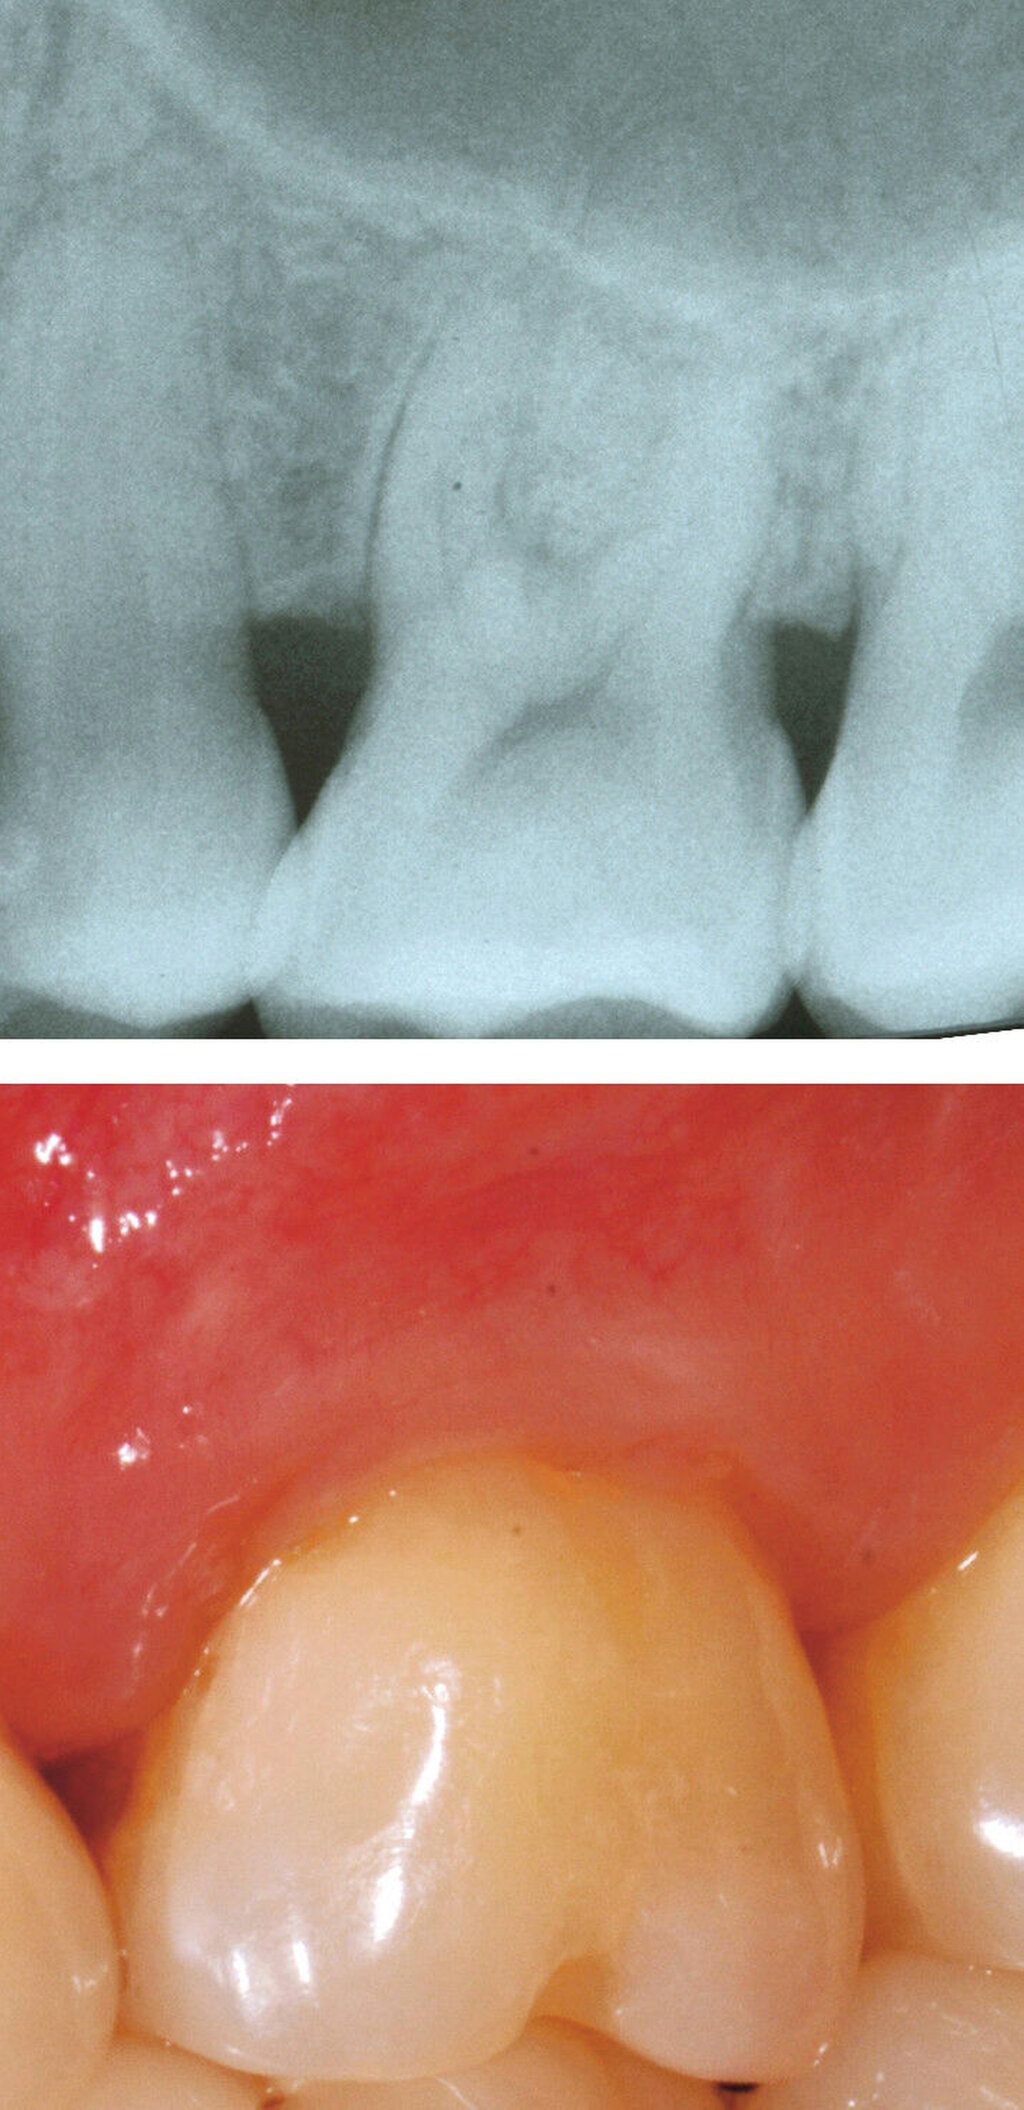

Evidenz aus humaner Histologie

Exemplarische humane Histologie ist der ultimative Beweis für ein regeneratives Heilungsergebnis und wird benötigt, um die aus klinischen Regenerationsstudien gewonnenen Informationen zu ergänzen [Machtei, 1997]. Der Nachweis einer parodontalen Regeneration erfordert den histologischen Nachweis von wiederhergestellten zahntragenden Geweben, einschließlich Zement, parodontalem Ligament und Alveolarknochen an einer zuvor Plaque-besiedelten Wurzeloberfläche. Obwohl solche Ergebnisse in gut kontrollierten experimentellen Tierstudien für eine Vielzahl von Behandlungsmodalitäten nachgewiesen worden sind, wurde bei der Überprüfung der histologischen Beweise für parodontale Regeneration in Furkationsdefekten festgestellt, dass begrenzte Informationen aus humaner Histologie vorliegen [Laugisch et al., 2019] und zwar für GTR [Gottlow et al., 1986; Stoller et al., 2001] eine Kombination aus GTR und KEM [Harris, 2002] und KEM [Camelo et al., 2003; Nevins et al., 2003].

2. Auswahl des Zahnes

Ein adäquater Zugang zum Operationsbereich und auch für die zukünftigen Mundhygienemaßnahmen ist äußerst wichtig. Molaren mit Grad-II-Furkationsdefekten (mandibulär und bukkal maxillär) sind Kandidaten, die für ein regeneratives Verfahren infrage kommen. Basierend auf der verfügbaren Evidenz sind interdentale Grad-II-Furkationsdefekte an Oberkiefermolaren deutlich weniger geeignet, höchstwahrscheinlich aufgrund des eingeschränkten Zugangs. Weitere lokale Charakteristika können Auswirkungen auf die Ergebnisse der regenerativen Furkationschirurgie haben. Zum Beispiel können ein dickerer Phänotyp und das Fehlen einer Weichgeweberezession die Heilung nach GTR-Verfahren positiv beeinflussen. Günstigere Ergebnisse sind an Stellen zu erwarten, an denen das verbleibende approximale Knochenniveau koronal zum Eingang beziehungsweise zum Dach des Furkationsdefekts liegt, verglichen mit solchen, bei denen das approximale Knochenniveau auf der Höhe oder apikal des Furkationseingangs liegt. Ein enger interradikulärer Abstand kann eine gründliche Defektinstrumentierung beeinträchtigen. Das Vorhandensein einer Wurzelkanalfüllung ist nicht per se eine Kontraindikation für die Furkationsregeneration – vorausgesetzt, es gibt keine Anzeichen für apikale pathologische Veränderungen.